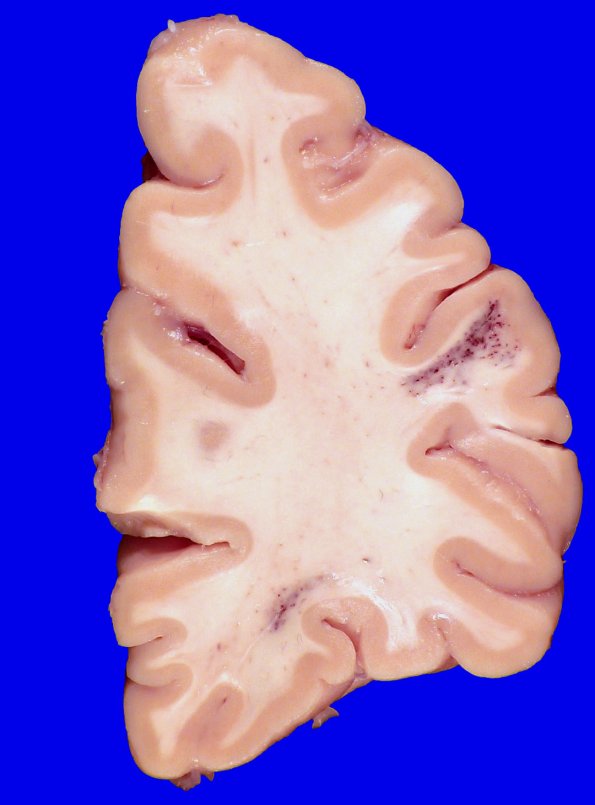

28A1,2, The subcortical location and individual vessels are easily visible with the naked eye. Although this is a typical location for venous angioma, the microscopic appearance is that of a telangiectasis. (H&E)